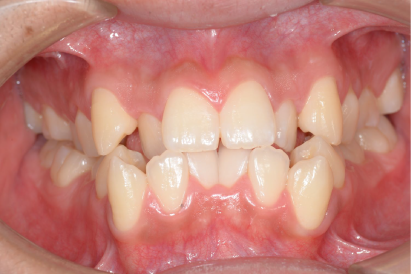

• 症例4

術前

*

術後

年代、性別

20代、男性

職業

学生

主訴

歯並び相談

部位

抜歯を併用してのインビザラインによる全顎矯正

治療期間

1年6ヶ月

矯正費用

95万円

施術説明

他院の矯正専門医院でマウスピース矯正は不可能と言われて、セカンドオピニオンで来院されました。就職活動が始まるまでに、歯並びを治療しておきたいということでしたが、当院の矯正専門医であるインビザライン・ファカルティーの山本先生による検査では、インビザラインで治療が可能と診断されました。抜歯を伴う矯正は通常長期にわたる事が多いですが、1年半で治療も完了し非常に喜んでもらえました。

副作用・リスク

なし